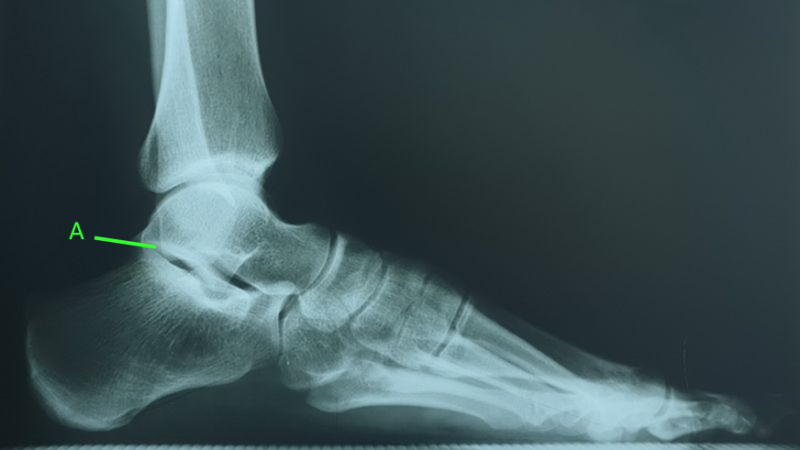

СКЛАДНИЙ СУГЛОБ (ЯК ВИЛКА). Є ВСІ ПЕРЕДУМОВИ ДЛЯ РОЗТЯГНЕННЯ ЗВ'ЯЗОК І ЗМІЩЕННЯ КІСТОК. РОЗПІЗНАЙТЕ СУГЛОБ.

варіанти відповідей

ДЕ ВИ БАЧИТЕ СУГЛОБ, ЯКИЙ ЗАБЕЗПЕЧУЄ РУХИ СТОПИ.

Запитання 56

СУГЛОБ УТВОРЕНИЙ СУГЛОБОВИМИ ПОВЕРХНЯМИ ЛАТЕРАЛЬНОЇ І МЕДІАЛЬНОЇ КІСТОЧКИ ТА ТІЛОМ ТАРАННОЇ КІСТКИ. РУХИ НАВКОЛО ФРОНТАЛЬНОЇ ОСІ. ЧАСТО - РОЗТЯЖІННЯ, ВИВИХИ, РОЗРИВИ, ПЕРЕЛОМИ. РОЗПІЗНАЙТЕ СУГЛОБ.

КОЛІННИЙ С.

ГОМІЛКОВО-СТОПНИЙ С.

КУЛЬШОВИЙ С.

ЛІКТЬОВИЙ С.

ПЛЕЧОВИЙ С.

ПРОМЕНЕВО-ЗАП'ЯСТКОВИЙ С.